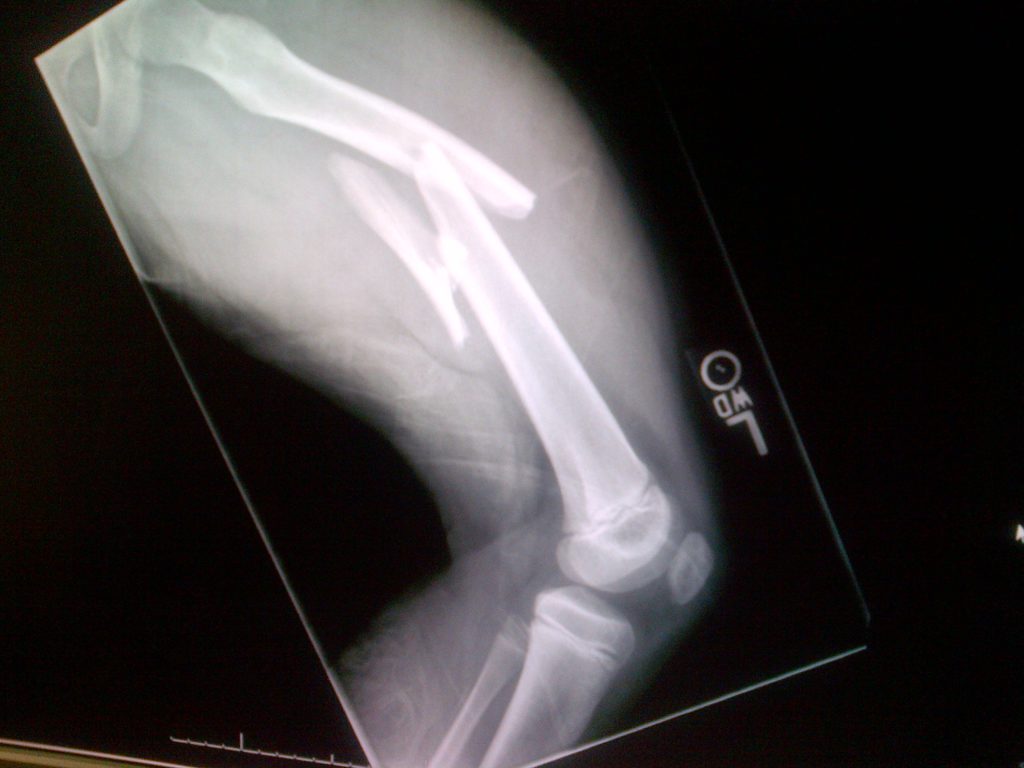

I've always loved to play sports. My main sport is soccer and I play 4 days a week 10 months a year and I also play on a travel basketball team. But I love just about any sport - tennis, skiing, waterskiing, baseball... I really love it all. On Super Bowl Sunday February 1st 2015 right after my 9th birthday, I went skiing with my Daddy. I was skiing down the mountain when I was pushed by another skier accidentally and ended up colliding with an unpadded metal pole in the ski run. Ouch! I was rushed to a trauma center with a severely shattered femur which needed emergency surgery to repair including putting a metal plate and 8 screws in my leg. I had a bunch of other complications and spent a while in the trauma center. After that I came back to New York City and was treated by Dr. Widmann. I was so used to doing so many sports and first I couldn't move then just walking was hard. I remember trying to move my leg a few inches took me a long time. I recovered from the break, but walked and ran with a limp and couldn't do what I used to on and off the field which made me sad. Over the course of the next year-and-a-half I have had surgery to remove the metal plate and 8 screws in my leg - Dr. Widmann did a great job - and had extensive rehabilitation as well as treatment for the scar. Some doctors had told me in the trauma center that I would never walk normally again but I didn't give up. Dr. Widmann help me regain my confidence and my physical therapist Josh was a rock star. I am back playing soccer, tennis, basketball and just went skiing for the first time in nearly two years since my accident. Everyone at Hospital for Special Surgery was nice, built my confidence, and gave me the best care. While I still have a big scar that reminds me of what happened, I'm stronger because of the experience. Nothing will stop me now! Thank you to everyone at HSS and especially to Dr. Widmann. Love, Caroline